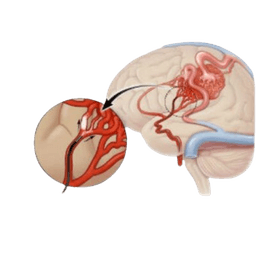

Cerebral of Brain Aneurysm

Cerebral aneurysm, also known as brain aneurysm, is a small and thin spot on the artery in the brain that bulges out and fills with blood. As a result, the bulging aneurysm leads to force or puts pressure on the nerves or brain tissue. This can also result in a burst, spilling blood surrounding tissue, known as hemorrhage. Consequently, a ruptured aneurysm can be a life-threatening condition, such as hemorrhagic stroke, brain damage, coma, or sometimes death.-br However, some cerebral aneurysms do not bleed, and are very small in size or cause other complications. These types of aneurysms are diagnosed while imaging tests for different medical problems. Cerebral aneurysms can take place anywhere in the brain, but most develop in major arteries along the base of the skull.-br Cerebral of brain aneurysms can develop at any age and anywhere in the brain. They are, however, most common in adults between the ages of 30 and 60 years, and are more common in females than males. Additionally, some patients are at high risk due to inherited disorders.